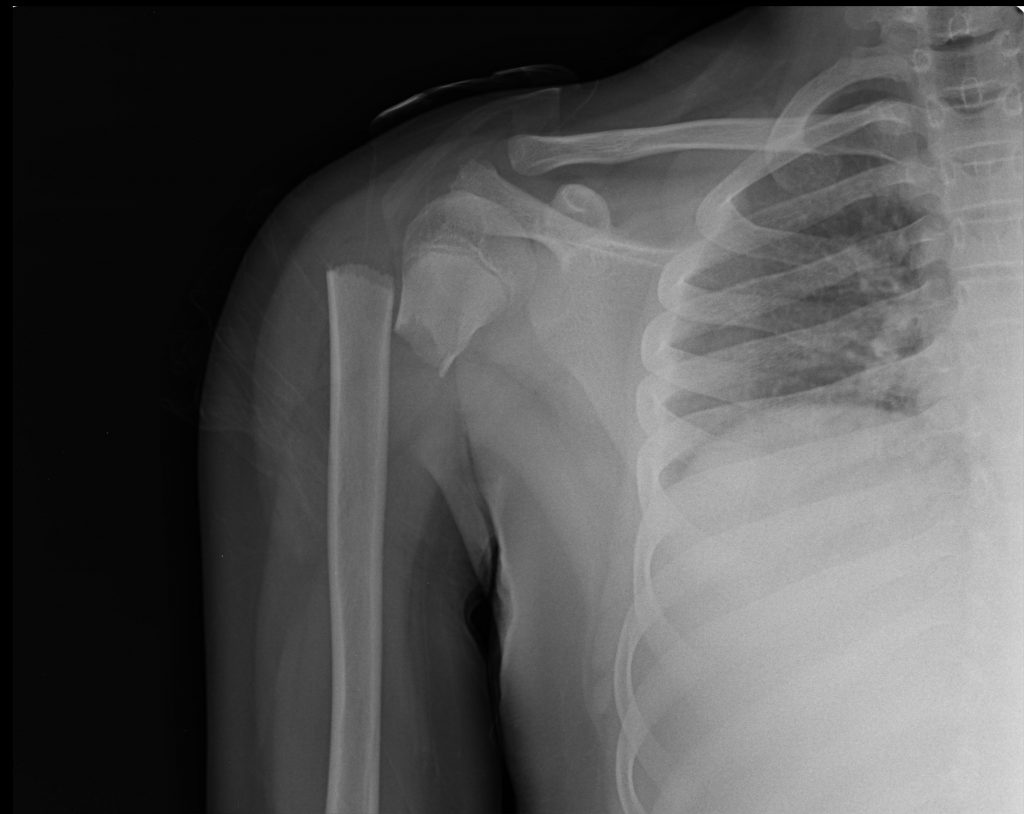

شکستگی بازو – Broken (Fractured) Upper Arm

این شکستگی یک آسیب جدی است. ممکن است در زمان تصادفات اتومبیل، ورزش و یا افتادن با دست باز ایجاد شود. این شکستگی معمولا شدیدا دردناک است. باید بیمار بلافاصله توسط پزشک ویزیت شود تا از آسیب های بعدی پیشگیری شود.

- ممکن است تصویر برداری با اشعه ایکس و یا تست های دیگری مثل سی تی اسکن و یا ام آر آی لازم شود.